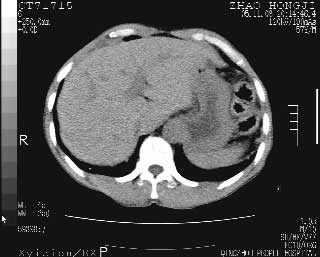

临床资料:男性,57岁,上腹部疼痛并5天,突然加重并延及全腹伴恶心5小时入院。胰淀粉酶化验在正常范围。检查:腹肌紧张,全腹压痛、反跳痛,尤以右上腹部为著。肠鸣音减低。血常规:wbc14.6x10/9, n:11.3x10/9 ,血压:135/90mmhg. 胸部透视:腹部肠腔轻度张气,未见其它异常改变。

从图提示我同意空腔脏器穿孔的诊断,来源肠道{由于病程较短,故没能见到肠系膜聚局的征象}。

肝缘见少许气体,胰尾部见少许气体包饶(蓝色圈),12指肠上部或球部邻近胆囊周边也可见少许气体影(黄色圈),并忖托出胆囊壁,12指肠远段肠道内未见明显气体(白色箭)。

消化道穿孔。12指肠球部周和胰周积气考虑12指肠穿孔可能性大。

腹腔内脂肪影密度增高,考虑腹膜炎

入院3小时后行剖腹探查术,见腹腔内大量脓性混浊液约1000ml,十二指肠球部溃疡穿孔,溃疡面约2.5x2cm,穿孔直径约0.6cm。胃内容物外益,周围组织炎性水肿明显。行十二指肠穿孔修补术。术后诊断:

1、十二指肠溃疡穿孔

2、弥漫性腹膜炎

对于少量的腹腔游离气体,ct检查较普通透视有绝对的优势,它不仅可以看到肝脏前上缘的气体,而且还能够看到小网膜区的游离气体。从而可以肯定诊断。各位分析战友的很好,感谢大家的参入!

少量气体时透视极有可能看不出来,ct确实有比透视明显的优势,使游离气体无处可藏。